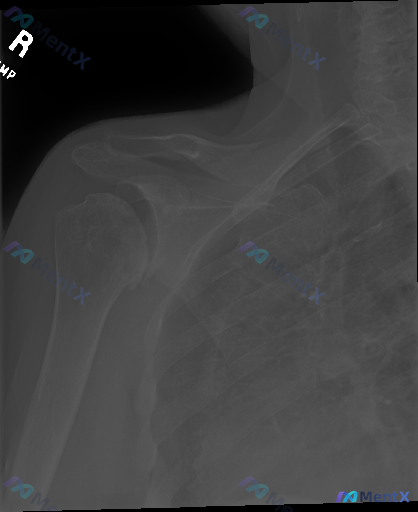

整理了一份右肩X光的影像分析资料,觉得这个「同影异病」的点很值得拿出来讨论。 先放影像客观描述: - 骨皮质:肱骨近端、肩胛带、锁骨远端连续,未见明确骨折线 - 关节:盂肱关节间隙、对合关系正常,无脱位半脱位,退行性变不显著 - 软组织:无明显肿胀 - 重点异常:肱骨大结节上方、冈上肌腱附着区域可见...